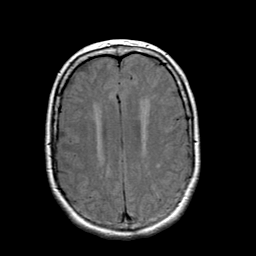

Stroke: proton density-weighted MR #1 -- Slice #17

[Home][Help][Clinical] Slice 17